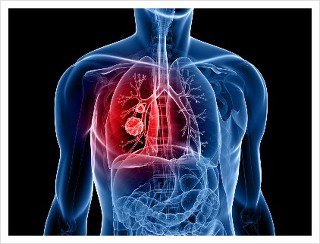

종양의 크기로 인해 직접 허리에 압력을 가해 허리의 중반부터 상층부까지 통증이 발생할 수 있습니다. 폐와 가슴 안쪽의 신경을 자극하여 통증이 매우 날카롭습니다. 이런 통증은 폐에서 척추로 악성 종양이 전이된 환자의 30%가 경험하고 있습니다.

부신에서 암이 전이 된 폐암 환자의 40%는 신장 바로 위에서 국부적인 통증을 경험했다고 말하고 있습니다. 이렇듯 폐암의 일반적인 증상과 허리 통증의 증상은 암의 위치에 따라 다양합니다.

폐암에서 뼈로 전이된 경우는 전체 환자의 40%이나 되며 보편적인 전이 부위는 척추와 다리의 큰 뼈입니다. 척추로 전이된 암의 경우는 뼈를 약하게 만들어 뼈가 부서지거나 압박 골절을 일으킬 수 있습니다. 이렇게 약해진 뼈가 골절되는 경우를 병적 골절이라고 합니다.